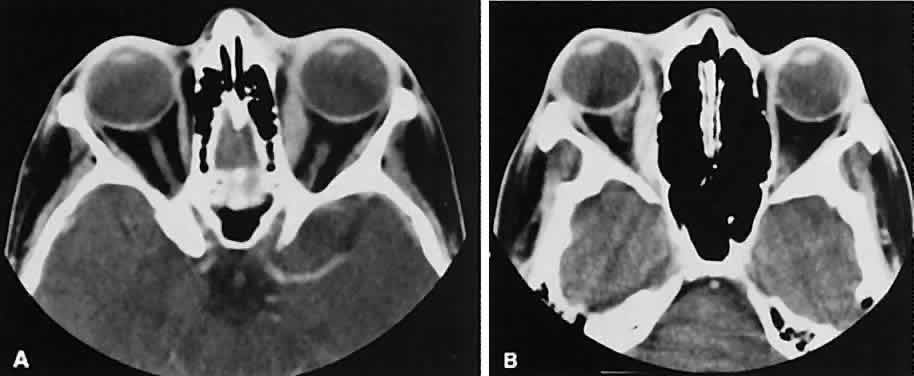

Dermoid cysts are located most frequently in the superior temporal quadrant of the orbit. They may be located anywhere within the orbital confines. Lesions in the lacrimal fossa or along the posterior lateral wall may communicate intracranially or into the temporalis fossa. Radiographically, the cysts are well-delineated and have lucent interiors with CT attenuation densities in the fat range (Fig. 19). Calcification along the rim of the cyst may be present. The bony changes have irregular, notched borders rather than the moth-eaten appearance associated with malignancy. The range of CT appearances can be quite wide.67

Fig. 19. Axial (A) and coronal (B) scans of a dermoid cyst. Note the low attenuation (lower than retrobulbar fat) within the well-demarcated cyst located in the right lacrimal gland fossa.